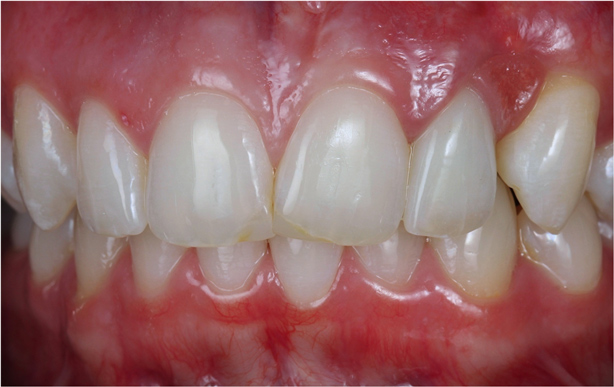

Once the healing was complete for the periodontal and dental implant procedures (Figure 22 and Figure 23), the final tooth preparations were completed and final impressions were made; records, including the electronic pantographic record, were then obtained. The treatment wax was used (Figure 24) to secure the patient’s approval of the esthetic design and to evaluate the esthetics and plan for the final prosthesis, including the cross-bite. The vertical dimension was raised, the facial anatomy was checked, and her speech and esthetics were checked by filming the patient and viewing facial profiles. Next, the implant abutments were made (Figure 25). In this case, metal–ceramic abutments were chosen; they were tried on before beginning the fabrication of the final restorations. These monolithic ceramic materials use lithium disilicate, which can result in a restoration with excellent biomechanical and esthetic properties (Figure 26 and Figure 27). The restorations were observed; the radiographs show the implants placed in the regenerated bone (Figure 28).

Figure 26 The healthy periodontal and dental implant foundation and gingival symmetry set the framework for the completion of the lithium-disilicate all-ceramic restorations.

Figure 26

Figure 27 The healthy periodontal and dental implant foundation and gingival symmetry set the framework for the completion of the lithium-disilicate all-ceramic restorations.

Figure 27